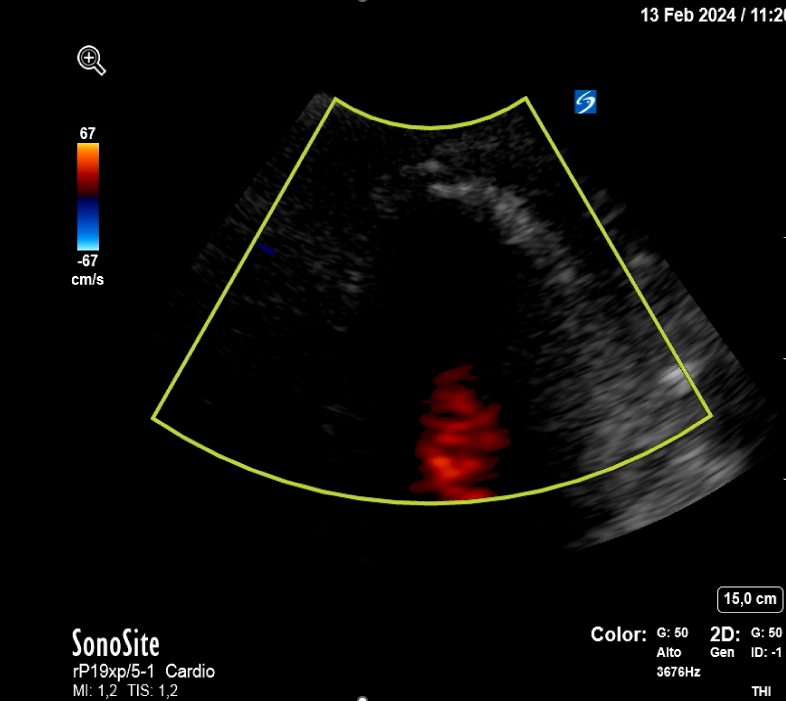

Se realiza interconsulta a Cardiología quien realiza una ecografía clínica cardíaca a pie de cama objetivando acinesia en ápex del ventrículo izquierdo con falta de continuidad a nivel septo-apical con flujo doppler compatible con rotura cardíaca a nivel de ápex que origina un derrame pericárdico moderado-severo, con colapso de ventrículo derecho.